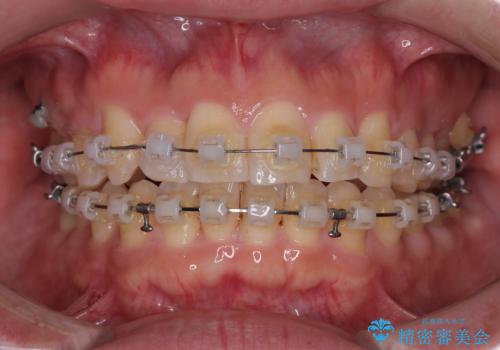

- クリアブラケット

- 1年1ヶ月

上顎前歯の舌側転位が顕著であったため、治療期間が長くなると思われましたが、僅か1年で無事に終えることができました。